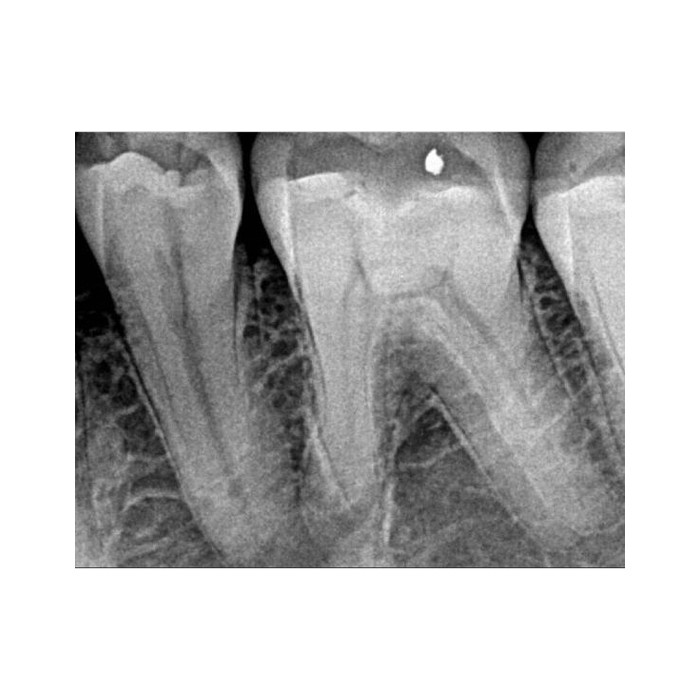

Ключевое преимущество RVG 5200 — высокая разрешающая способность 16 пар линий/мм. Это означает исключительную детализацию снимка, позволяющую четко визуализировать анатомические структуры, тонкие корневые каналы, начальные стадии кариеса и минимальные изменения в периапикальных тканях. Ваша диагностика становится более точной и уверенной.

В чем разница между 16 пар/мм и другими показателями разрешения?

Разрешение в парах линий на миллиметр (пл/мм) — это объективный параметр, характеризующий способность системы различать мелкие детали. Показатель 16 пл/мм является высоким и обеспечивает отличную диагностическую информативность снимков, необходимую для эндодонтии, пародонтологии и выявления скрытого кариеса.